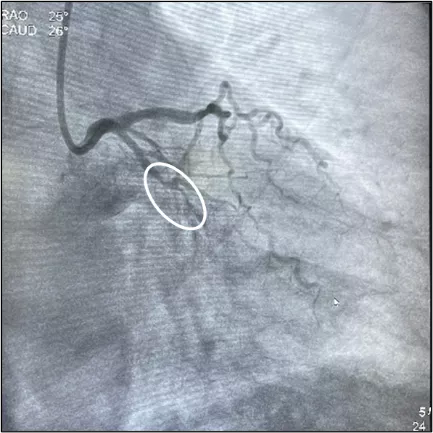

患者刘某,因反复胸闷、气短4年,加重1周入院治疗,考虑其为冠心病,在完善冠脉造影提示:心脏后面的旋支血管中段100%闭塞。

经过与家属沟通后,心脏泛血管病院冠心病中心团队马上开始了紧张地准备工作,通过使用微导管支撑、平行导丝、双腔微导管辅助技术,最终顺利打通了闭塞血管。但第二个难题随之而来,打通的血管处刚好存在一个较大的分叉病变,分支开口也有80%狭窄,如果要在分支也植入支架,有可能带来手术时间延长,支架数量过多,口服抗血小板药物多,远期预后不良,血栓发生率高等问题。冠心病中心团队经过讨论决定,采用分支药物球囊处理,主支支架Crossover技术,必要时进行斑块、血管嵴修饰或支架植入,最终顺利达成分支无植入,完成了手术。

术前

术后